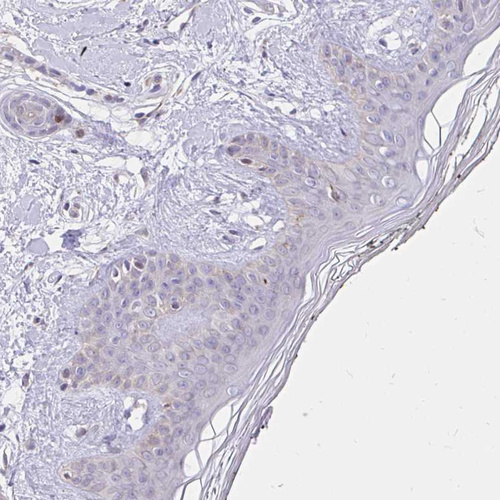

Immunohistochemical staining of human testis shows strong membranous and cytoplasmic positivity in cells in seminiferous ducts.